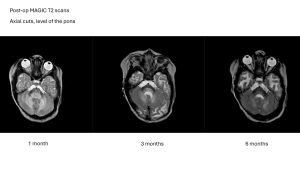

In September 2025, our landmark study proving that MYR-101 successfully restored myelin and reduced toxic NAA levels in children was published.